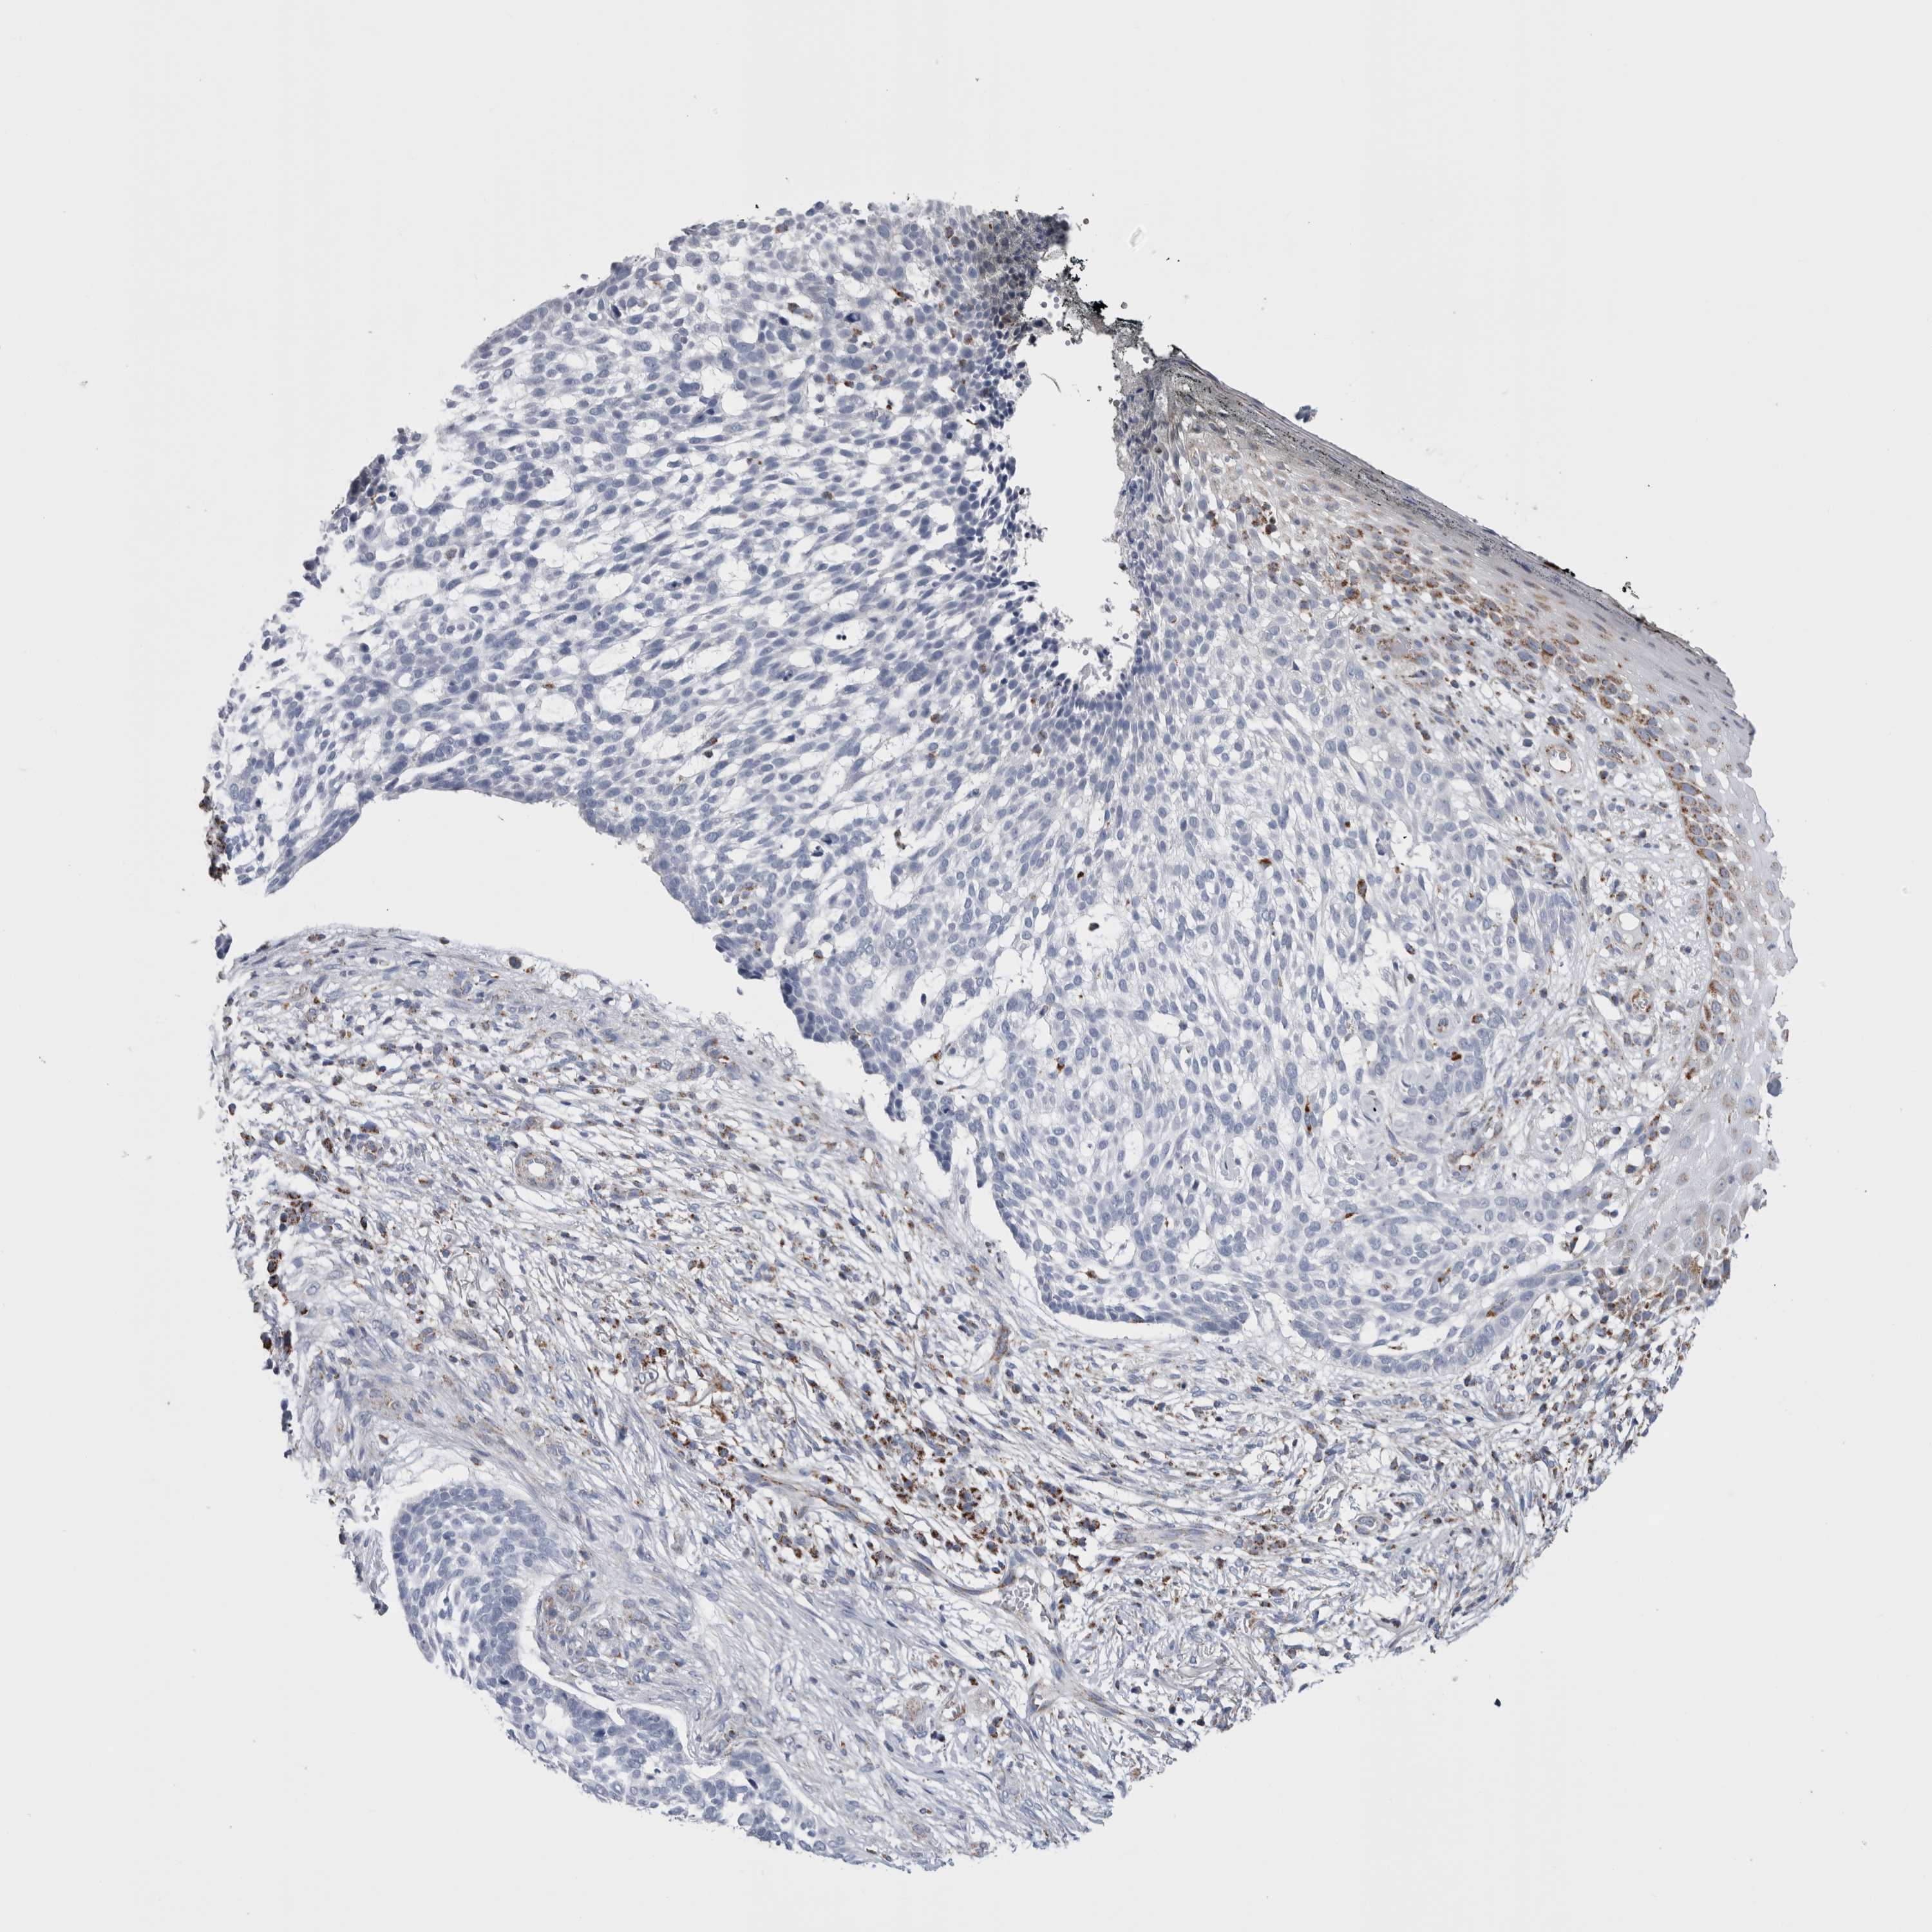

SKIN CANCER - Protein expressioni

A mouse-over function shows sample information and annotation data. Click on an image to view it in a full screen mode. Samples can be filtered based on level of antibody staining by selecting one or several of the following categories: high, medium, low and not detected. The assay and annotation is described here.

Each image is clickable and will lead to virtual microscopy that enables deeper exploration of all samples and also displays staining intensity scores, fraction scores and subcellular localization as well as patient and tissue information for each sample.

Antibody HPA024089

Staining

Low

Moderate

75%-25%

Cytoplasmic/membranous

Squamous cell carcinoma, NOS